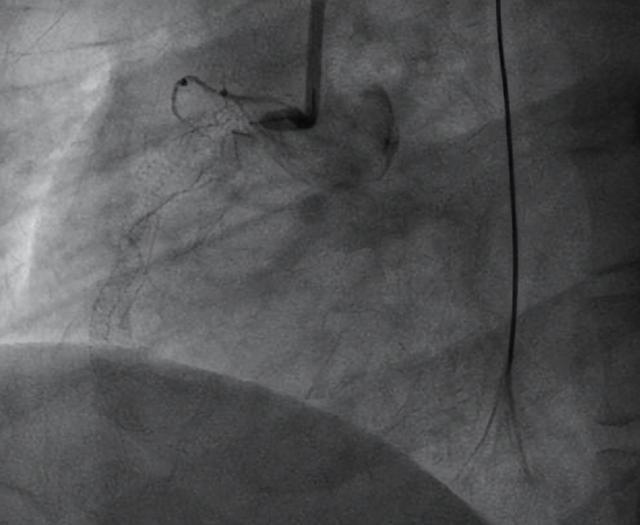

经当地医院治疗一周后转入中南大学湘雅三医院心内科,复查冠脉造影示:右冠支架内完全闭塞(图1)。经科室讨论后,认为传统冠脉内抽栓及溶栓无法解决该患者的顽固性机化血栓问题,决定采用目前治疗冠脉机化血栓最先进的技术—准分子激光消融导管(ELCA)进行治疗。

▲图1:右冠支架内完全闭塞